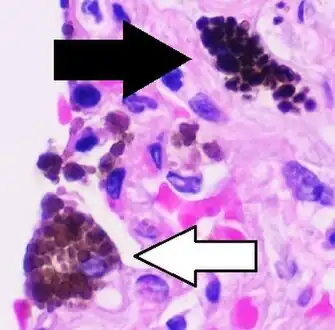

Micrograph of anthracosis, with interstitial pigment deposition black arrow and an anthracotic macrophage

Coal dust is not as fibrogenic as silica dust.[11] Coal dust that enters the lungs can neither be destroyed nor removed by the body. The particles are engulfed by resident alveolar macrophages or interstitial macrophages and remain in the lungs, residing in the connective tissue or pulmonary lymph nodes. Coal dust provides a sufficient stimulus for the macrophage to release various products, including enzymes, cytokines, oxygen radicals, and fibroblast growth factors,[12] which are important in the development of inflammation and fibrosis in BLD. Aggregations of carbon-laden macrophages can be visualized under a microscope as granular, black areas. In serious cases, the lung may grossly appear black. These aggregations can cause inflammation and fibrosis, as well as the formation of nodular lesions within the lungs. The centers of dense lesions may become necrotic due to ischemia, leading to large cavities within the lung.

Simple BLD is marked by the presence of 1–2 mm nodular aggregations of anthracotic macrophages, supported by a fine collagen network, within the lungs. Those 1–2 mm in diameter are known as coal macules, with larger aggregations known as coal nodules. These structures occur most frequently around the initial site of coal dust accumulation—the upper regions of the lungs around respiratory bronchioles.[2] The coal macule is the basic pathological feature of BLD and has a surrounding area of enlargement of the airspace, known as focal emphysema.[13][14] Focal emphysema extends into progressive centrilobular emphysema. Less commonly a variant of panacinar emphysema develops.[15]